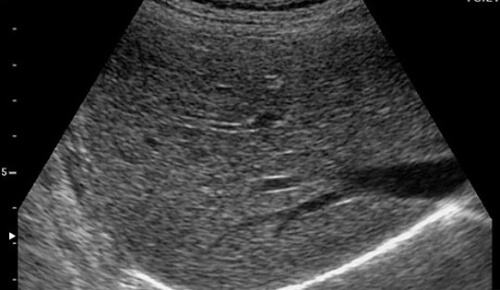

那么到底肝脏里面有没有脂肪呢?这一点医学早就证实:人体都是由细胞组成的,肝脏也是由一个一个肝细胞构建起来的,在每一个细胞里,都含有必不可少的构成细胞的基本成份或者是物质、材料,那就是蛋白质、脂肪、糖,所以每个肝细胞都会有脂肪存在,只是因人而宜,脂肪在肝细胞里的含量多少不同而已。脂肪肝(fatty liver)是指各种原因引起的肝细胞内脂肪堆积而言。正常人每100克肝脏湿重约含4~5克脂质。目前医学上确定的标准是:肝细胞里含有的脂肪在5%以下,被列为正常;如果含量在30%以上,可以称为肝的脂肪变性,或者是脂肪堆积,才称为脂肪肝。那么脂肪肝的证实、明确,不是靠超声、CT、核磁,不是靠这些影像学的方法来判断肝细胞里有多少脂肪,仅靠影像学的所见诊断脂肪肝是不准确的。就拿超声检查来说,正常肝与脂肪肝的区别不是那么可靠的。(图1、2)

图1 正常肝脏的超声图像